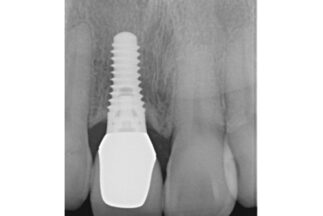

| 治療内容 | 右側上顎中切歯を抜歯しインプラント埋入をおこなった。上部構造装着後12年経過。 |

| リスクについて | 歯肉の退縮等、審美面でのリスク。 |